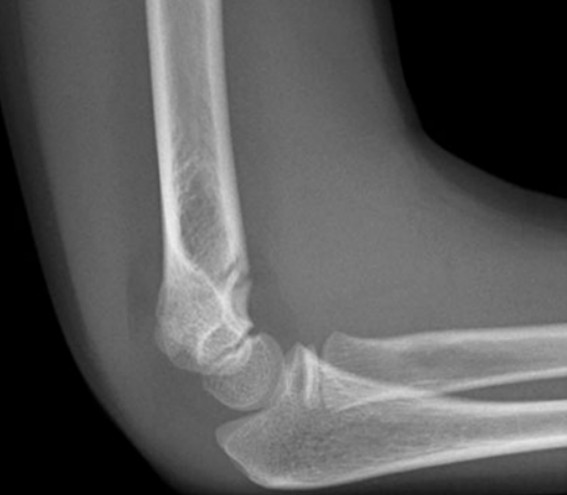

Supracondylar humerus fracture

A 5-year-old girl presents after falling from monkey bars and injuring her right elbow. A lateral X-ray of the elbow …

Elbow injury

You are the ED consultant in a regional centre when a 30-year-old male presents with an isolated left elbow injury …